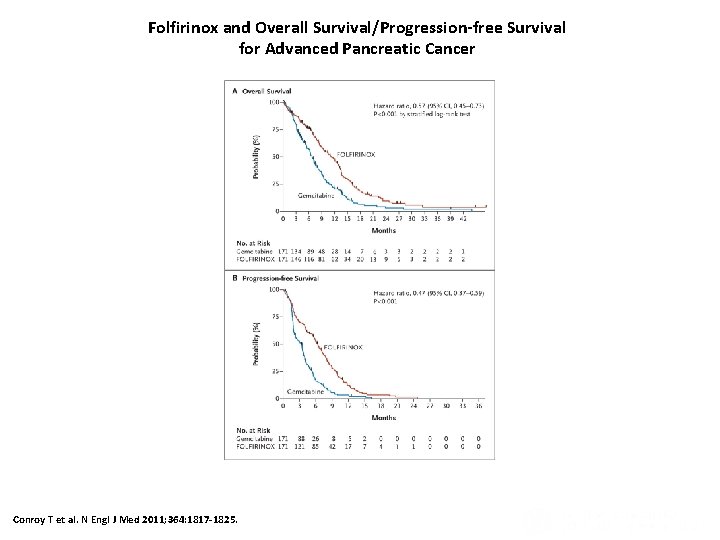

Folfirinox and Overall Survival/Progression-free Survival for Advanced Pancreatic Cancer Conroy T et al. N Engl J Med 2011; 364: 1817 -1825.